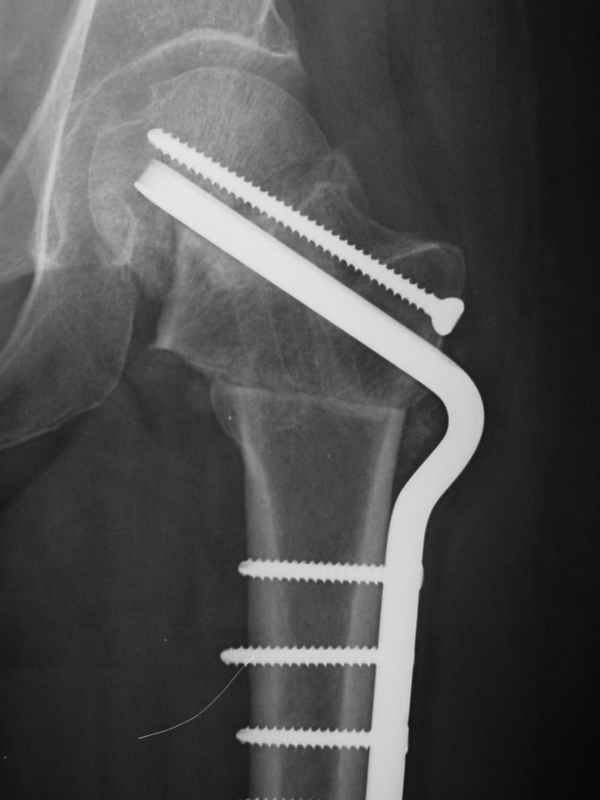

dhs will not correct improper biomechanical environment and may further compromise vascular

integrity consider establish vascular status via mri

and if viable follow with proximal valgus osteotomy

case provided s/p failed fixation